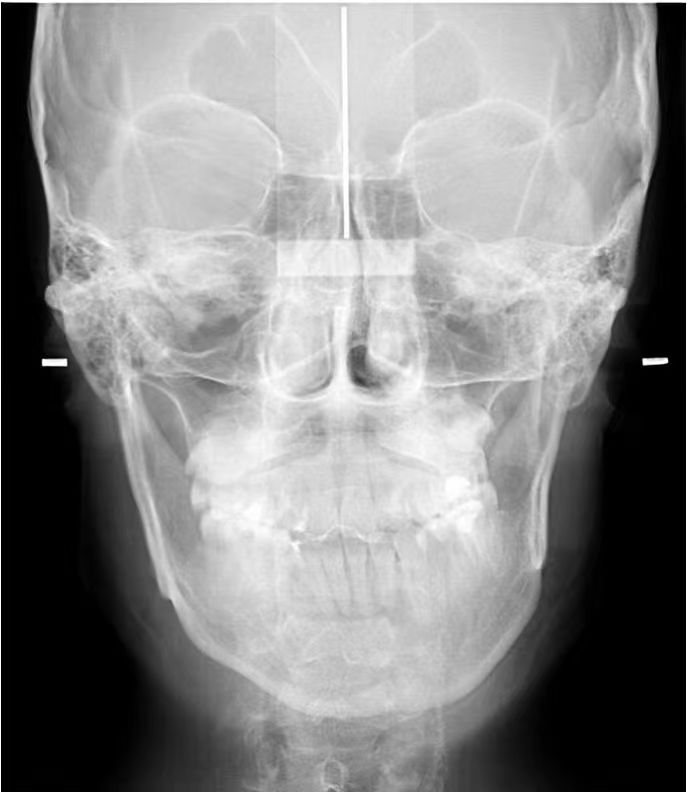

情况:不接受外科手术,在当地做了1年半的矫治,遇到困难无法进行。由外地正畸同行推荐来上海寻求非手术矫治的二手病例。武广增老师接收时的错合畸形情况,呈现严重的骨性反合偏合及侧方开合(图1-图10)。由于推荐其去口腔医院接受正颌外科手术遭到拒绝,武广增老师通过专业的检查、分析,制定一套详细的治疗计划,采用了磨牙推进器技术、武式辅弓技术等特色正畸手段获得明显效果(图2-1~图2-9)。治疗结束后也拍摄了相关照片(图3-1~图3-9)。

矫治前

图2